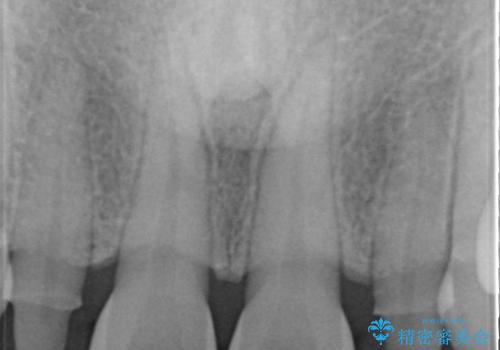

- 歯の形が気になるということで以前入っていたプラスチックのものから、セラミックでの治療を希望されたので行いました。

色や形をこだわりたいということで、当院最上位ランクのエクセレントにて治療を行いました。

以前使用していた被せ物を除去して、仮歯に置き換えます。

その後、歯の最終的な形を作って型取りを行います。